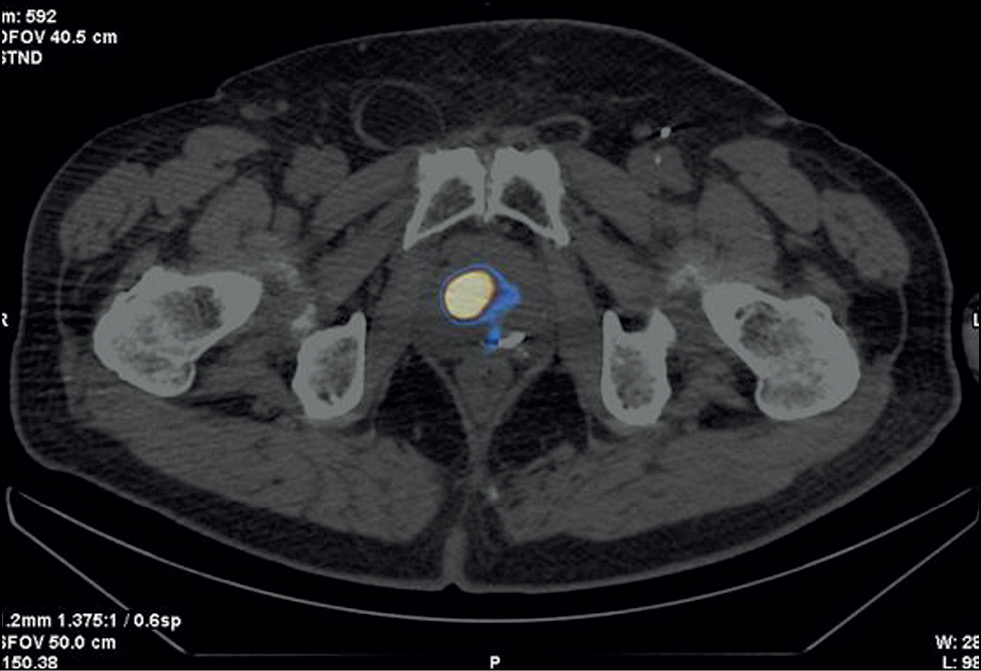

Case report 4

Patient F., 68 years old, was admitted with prostate cancer, T3a, which had spread to the prostate gland capsule. In 2013, 125I sources were implanted into the prostate tissue and the extracapsular area. PSA has increased since the end of 2020. SPECT/CT was performed using 99mTc-HYNIC-PSMA due to an increased PSA level of 0.95–2.8 ng/mL after the previous treatment (Figure 5). SPECT/CT revealed a 15-mm3 site of tumor tropic RP accumulation, which was biopsied under the CT guide. A histological diagnosis was prostate adenocarcinoma, Gleason 6 (3 + 3). Dosimetry planning for low-dose brachytherapy was performed using SPECT/CT. On November 03, 2021, 125I microsources were re-implanted according to topometric markings to implement the dosimetry plan. The PSA level was 0.05 ng/mL during the follow-up examination (January 23, 2023).

Fig. 5. Patient F., 68 years old, SPECT/CT with 99mTc-HYNIC-PSMA: Sites of radiopharmaceutical accumulation at the border of the central zone and the posterolateral part of the peripheral zone on the right side at the level of the base of the right prostate lobe. The scan visualizes multiple rods in the prostate gland, implanted during previous brachytherapy.

In this case, SPECT/CT with 99mTc-HYNIC-PSMA allowed for a precision biopsy, which confirmed the local recurrence of prostate cancer and subsequently enabled brachytherapy to be repeated (salvage) under the CT guide.